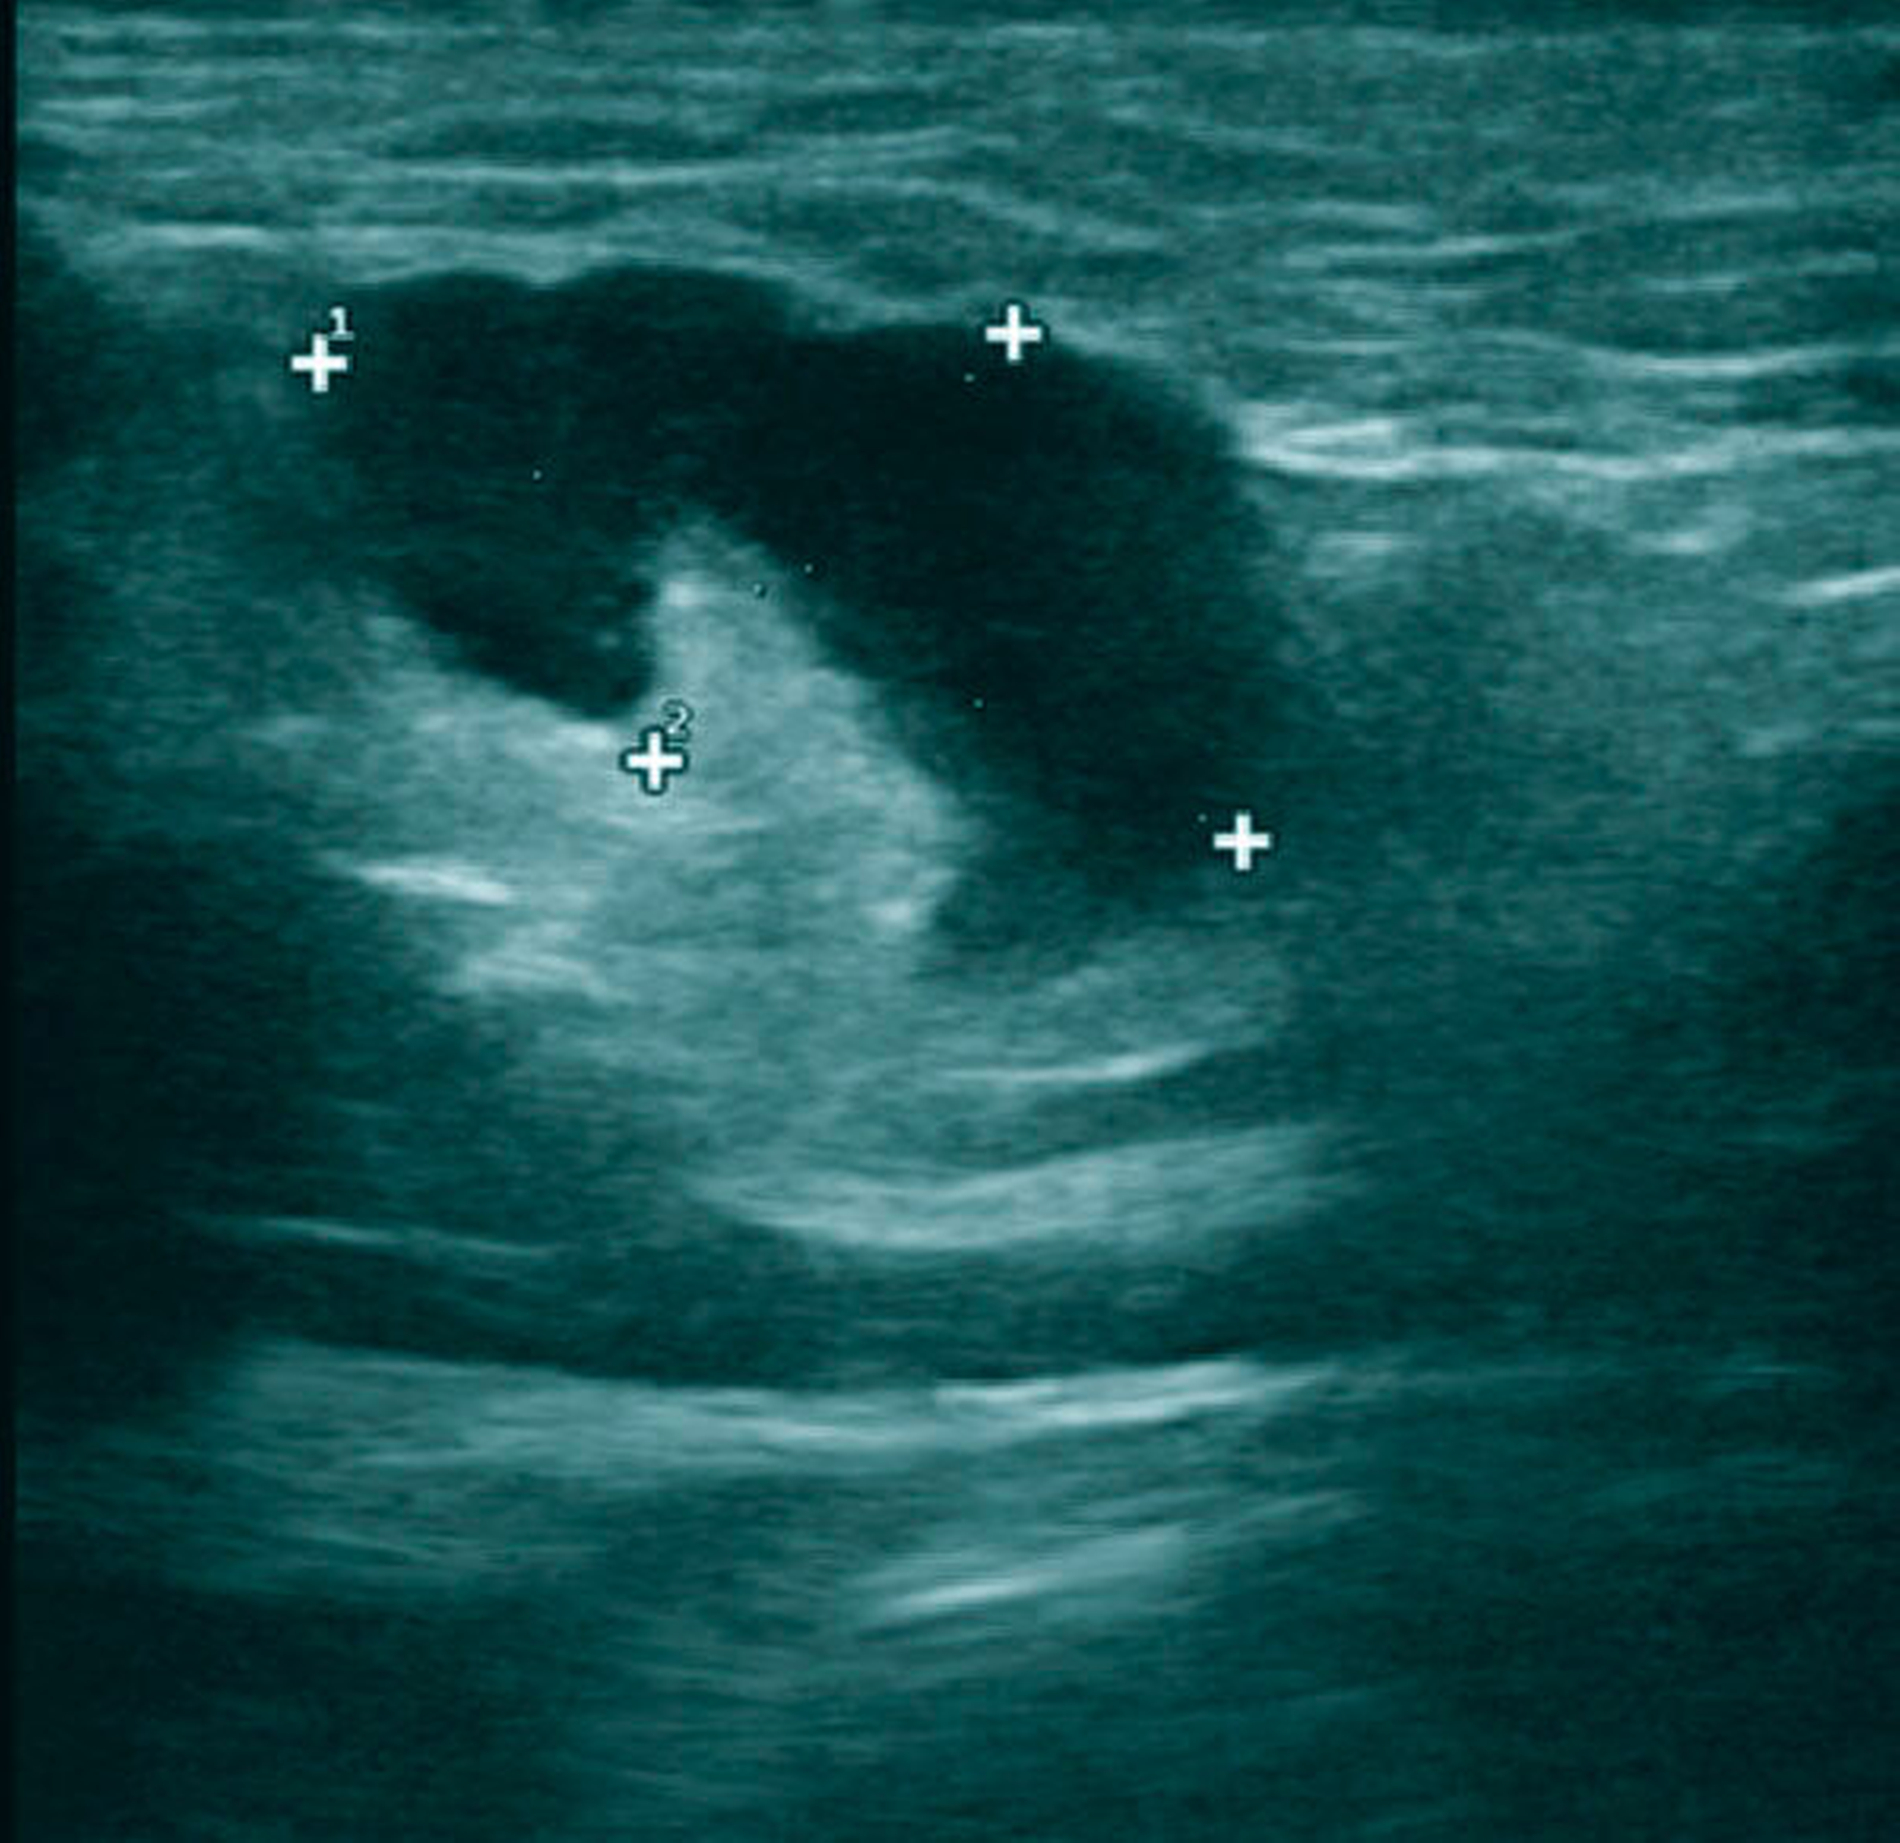

Die serologische Blutuntersuchung ergab eine starke Erhöhung der C-reaktiven Proteine und der Leukozyten. Im Ultraschall und in der Kontrastmittel-verstärkten Computertomografie (CT) ließ sich eine Vergrößerung der zervikalen Lymphknoten darstellen (Abbildungen 1 und 2). Weitere Befunde oder Foci ließen sich nicht nachweisen.

Die klinische Diagnostik ist bei der Lymphknotentuberkulose von enormer Bedeutung, da sie bei Bestehen einer B-Symptomatik (Nachtschweiß, Müdigkeit, Gewichtsverlust) nicht selten mit akuten Infekten wie etwa der Influenza verwechselt wird. Die Ausprägung der Symptomatik ist allerdings patientenabhängig, sodass die Infektion aufgrund eines möglichen atypischen Verlaufs unerkannt bleiben und sogar letal enden kann [Kalaidina et Holbrook, 2018]. Bildgebende Verfahren wie Ultraschall, CT, MRT oder minimal-invasive Eingriffe wie die Feinnadelaspiration – die aber wegen der Verschleppung von Zellen kontrovers diskutiert wird – können aufschlussreich sein. Mikrobiologische und molekulare evaluierte Verfahren sind Nukleinsäure-amplizierende Tests (zum Beispiel PCR), Interferon-Gamma-Release-Assays (zum Beispiel der Quantiferon-Test, TB-Spot-Test), Kulturanlegung und mikroskopische Untersuchungen von Exzisionsbiopsien. Die mikrobiologische Diagnostik mit Kultivierung der Bakterien ist die Methode der Wahl (Goldstandard), da sie zum einen die Bestimmung der mykobakteriellen Spezies und zum anderen die Untersuchung auf medikamentöse Unverträglichkeiten und Resistenzen erlaubt [Schaberg et al., 2017].